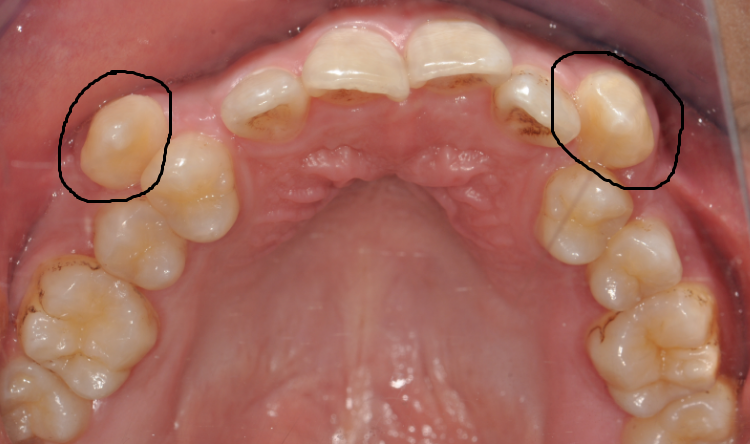

齒 嘿嘿,牙妹,我覺得我的牙齒距離就差一點兒了。你看我的虎牙,長出來的位置不正,被擠在牙弓外面,一張嘴就會看見,很不美觀。別的牙還挺齊的,所以我想能不能直接把虎牙拔掉,這樣就用簡單的方法解決了問題。(圖片1 2)